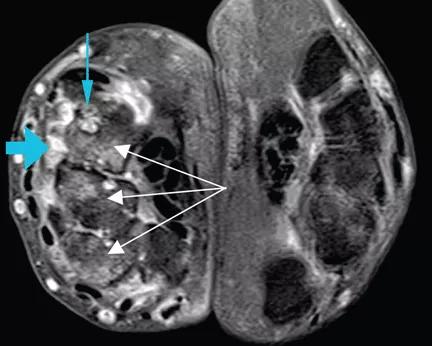

A 47-year-old man who had been diagnosed with rheumatoid arthritis 5 years previously was referred to us for management of bilateral pleural effusions. At the time of his diagnosis, his symptoms included pain and swelling of both wrists and the metacarpal joints of both hands. His serum C-reactive protein level had been elevated at that time, but he had no detectable rheumatoid factor. Findings on magnetic resonance imaging of the hand were very suggestive of rheumatoid arthritis (See image above: Axial T1-weighted magnetic resonance imaging with gadolinium contrast shows synovitis (large blue arrow) along the dorsal aspect of the wrist. Also seen are erosions in the carpal bones (thin blue arrow) and bone marrow edema (white arrows), which is asymmetrical compared with the other wrist, a finding highly suggestive of rheumatoid arthritis.). He had been started on the anti-tumor necrosis factor agent etanercept but his symptoms improved only slightly, and therefore a glucocorticoid had been added. Two years later, he developed abdominal pain, for which he underwent cholecystectomy. However, he continued to have chronic, generalized abdominal pain, and over the next 4 years he lost 25 lb. Upper endoscopy showed no mucosal changes, and multiple random biopsy samples were obtained for histologic evaluation (Figure) as part of his workup for chronic abdominal pain.